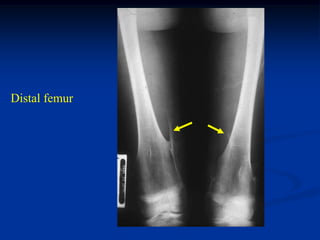

Case #550

59 year female

enchondroma

distal femur